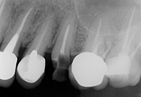

拔牙洞保存術,是在拔牙之後,於拔牙洞內填補再生骨粉,保持齒槽嵴寬度與高度的術式。術後,齒槽骨可大量保留,並保持其高度,增加軟組織。沒有實行拔牙窩洞保存術,骨質會迅速流失,流失的骨質將難以恢復到原來的形狀。

在植牙及製做假牙時,需要良好的齒槽骨支持,才可延長植牙的成功率及使用的壽命。因此能在拔牙時填補骨粉,會是保存骨質最好、最重要的時機。